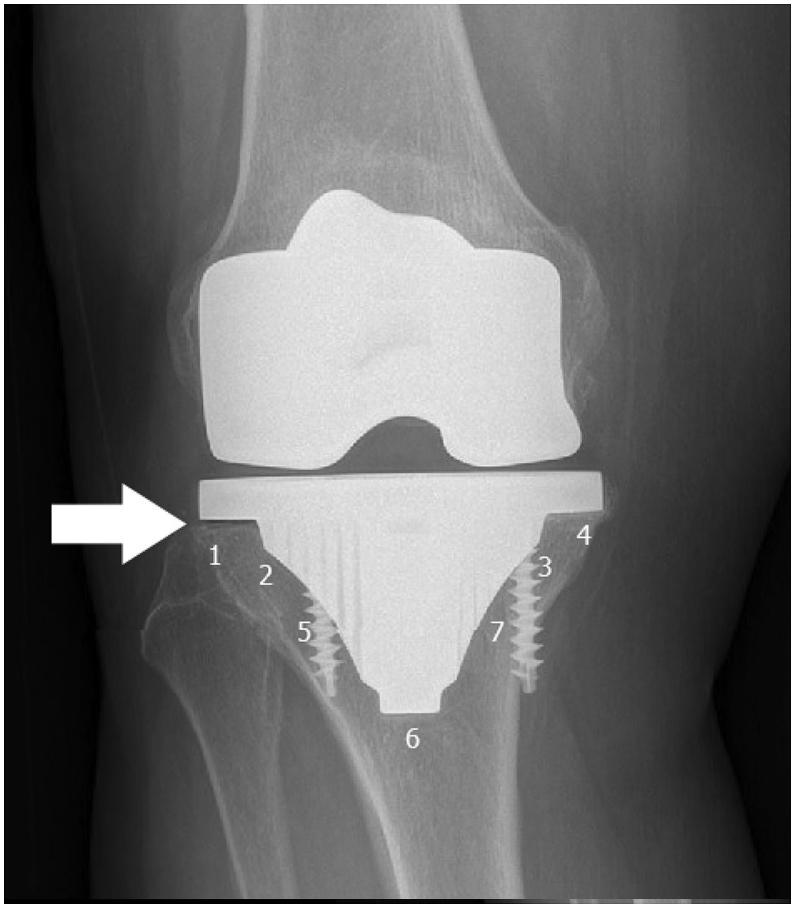

A total of 51 knees of 49 patients (33 female and 16 male; mean age: 61.6 years (range, 29-66 years)) who underwent TKR surgery with a posterior stabilized hydroxyapatite coated knee implant were included in this study. All of the tibial components were fixed with screws. The HSS scores were examined preoperatively and at the final follow-up. Radiological assessment was performed with Knee Society evaluating and scoring system. Kaplan-Meier survival analysis was performed to rule out the survival of the tibial component.

The mean HSS scores were 45.8 (range 38-60) and 88.1 (range 61-93), preoperatively and at the final follow-up respectively. Complete radiological assessment was performed for 48 knees. Lucent lines at the tibial component were observed in 4 patients; one of these patients underwent a revision surgery due to the loosening of the tibial component. The 10-year survival rate of a tibial component was 98%.

Cementless total knee replacement has satisfactory long term clinical results. Primary fixation of the tibial component with screws provides adequate stability even in elderly patients with good bone quality.

方法

本研究纳入了49例患者的51个膝关节(33例女性和16例男性;平均年龄:61.6岁(范围,29 - 66岁)),这些患者接受了后稳定型羟基磷灰石涂层膝关节假体的全膝关节置换术。所有胫骨组件均用螺钉固定。术前和末次随访时检查HSS评分。采用膝关节协会评估和评分系统进行影像学评估。进行Kaplan-Meier生存分析以排除胫骨组件的生存率。

术前和末次随访时的平均HSS评分分别为45.8(范围38 - 60)和88.1(范围61 - 93)。对48个膝关节进行了完整的影像学评估。4例患者观察到胫骨组件处有透亮线;其中1例患者因胫骨组件松动接受了翻修手术。胫骨组件的10年生存率为98%。

结论